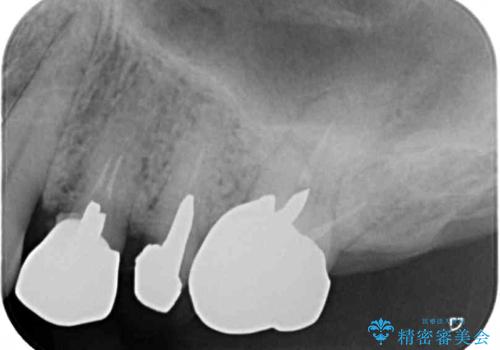

診察をしたところ、上下大臼歯の歯肉に排膿路認められたため、根管治療を行い、その後補綴治療を行うこととしました。

また、上顎の欠損部位にはインプラント治療を行うこととしました。

改めて診療を行ったところ、歯根破折が認められ、抜歯後にインプラント治療を行うこととしました。

下顎大臼歯の抜歯決断までに時間がかかったため、治療期間はやや長くなりましたが、安定した咬み合わせとなり、痛みもなく安心して噛めるようになりました。